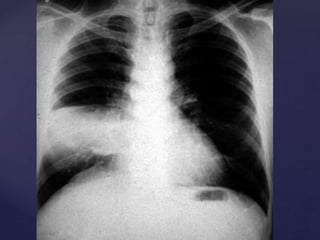

CONFIRMAMOS EL

DIAGNÓSTICO:

RADIOGRAFÍA DE TÓRAX FRENTE Y PERFIL

Neumonía por Mycoplasma Pn.